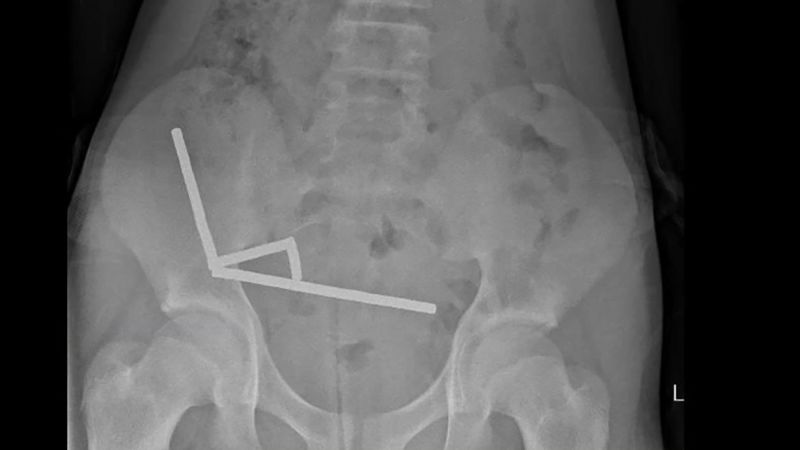

Diagnostic scans indicated that the magnets had formed into four chains within the lower-right quadrant of the abdomen, pulling various sections of the bowel together through their magnetic attraction, which in some cases distorted imaging. This prompted doctors to conduct exploratory surgery.